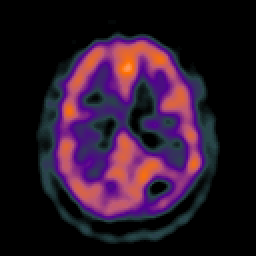

Glioma overlay -- Slice #19

[Home][Help][Clinical] Slice 19